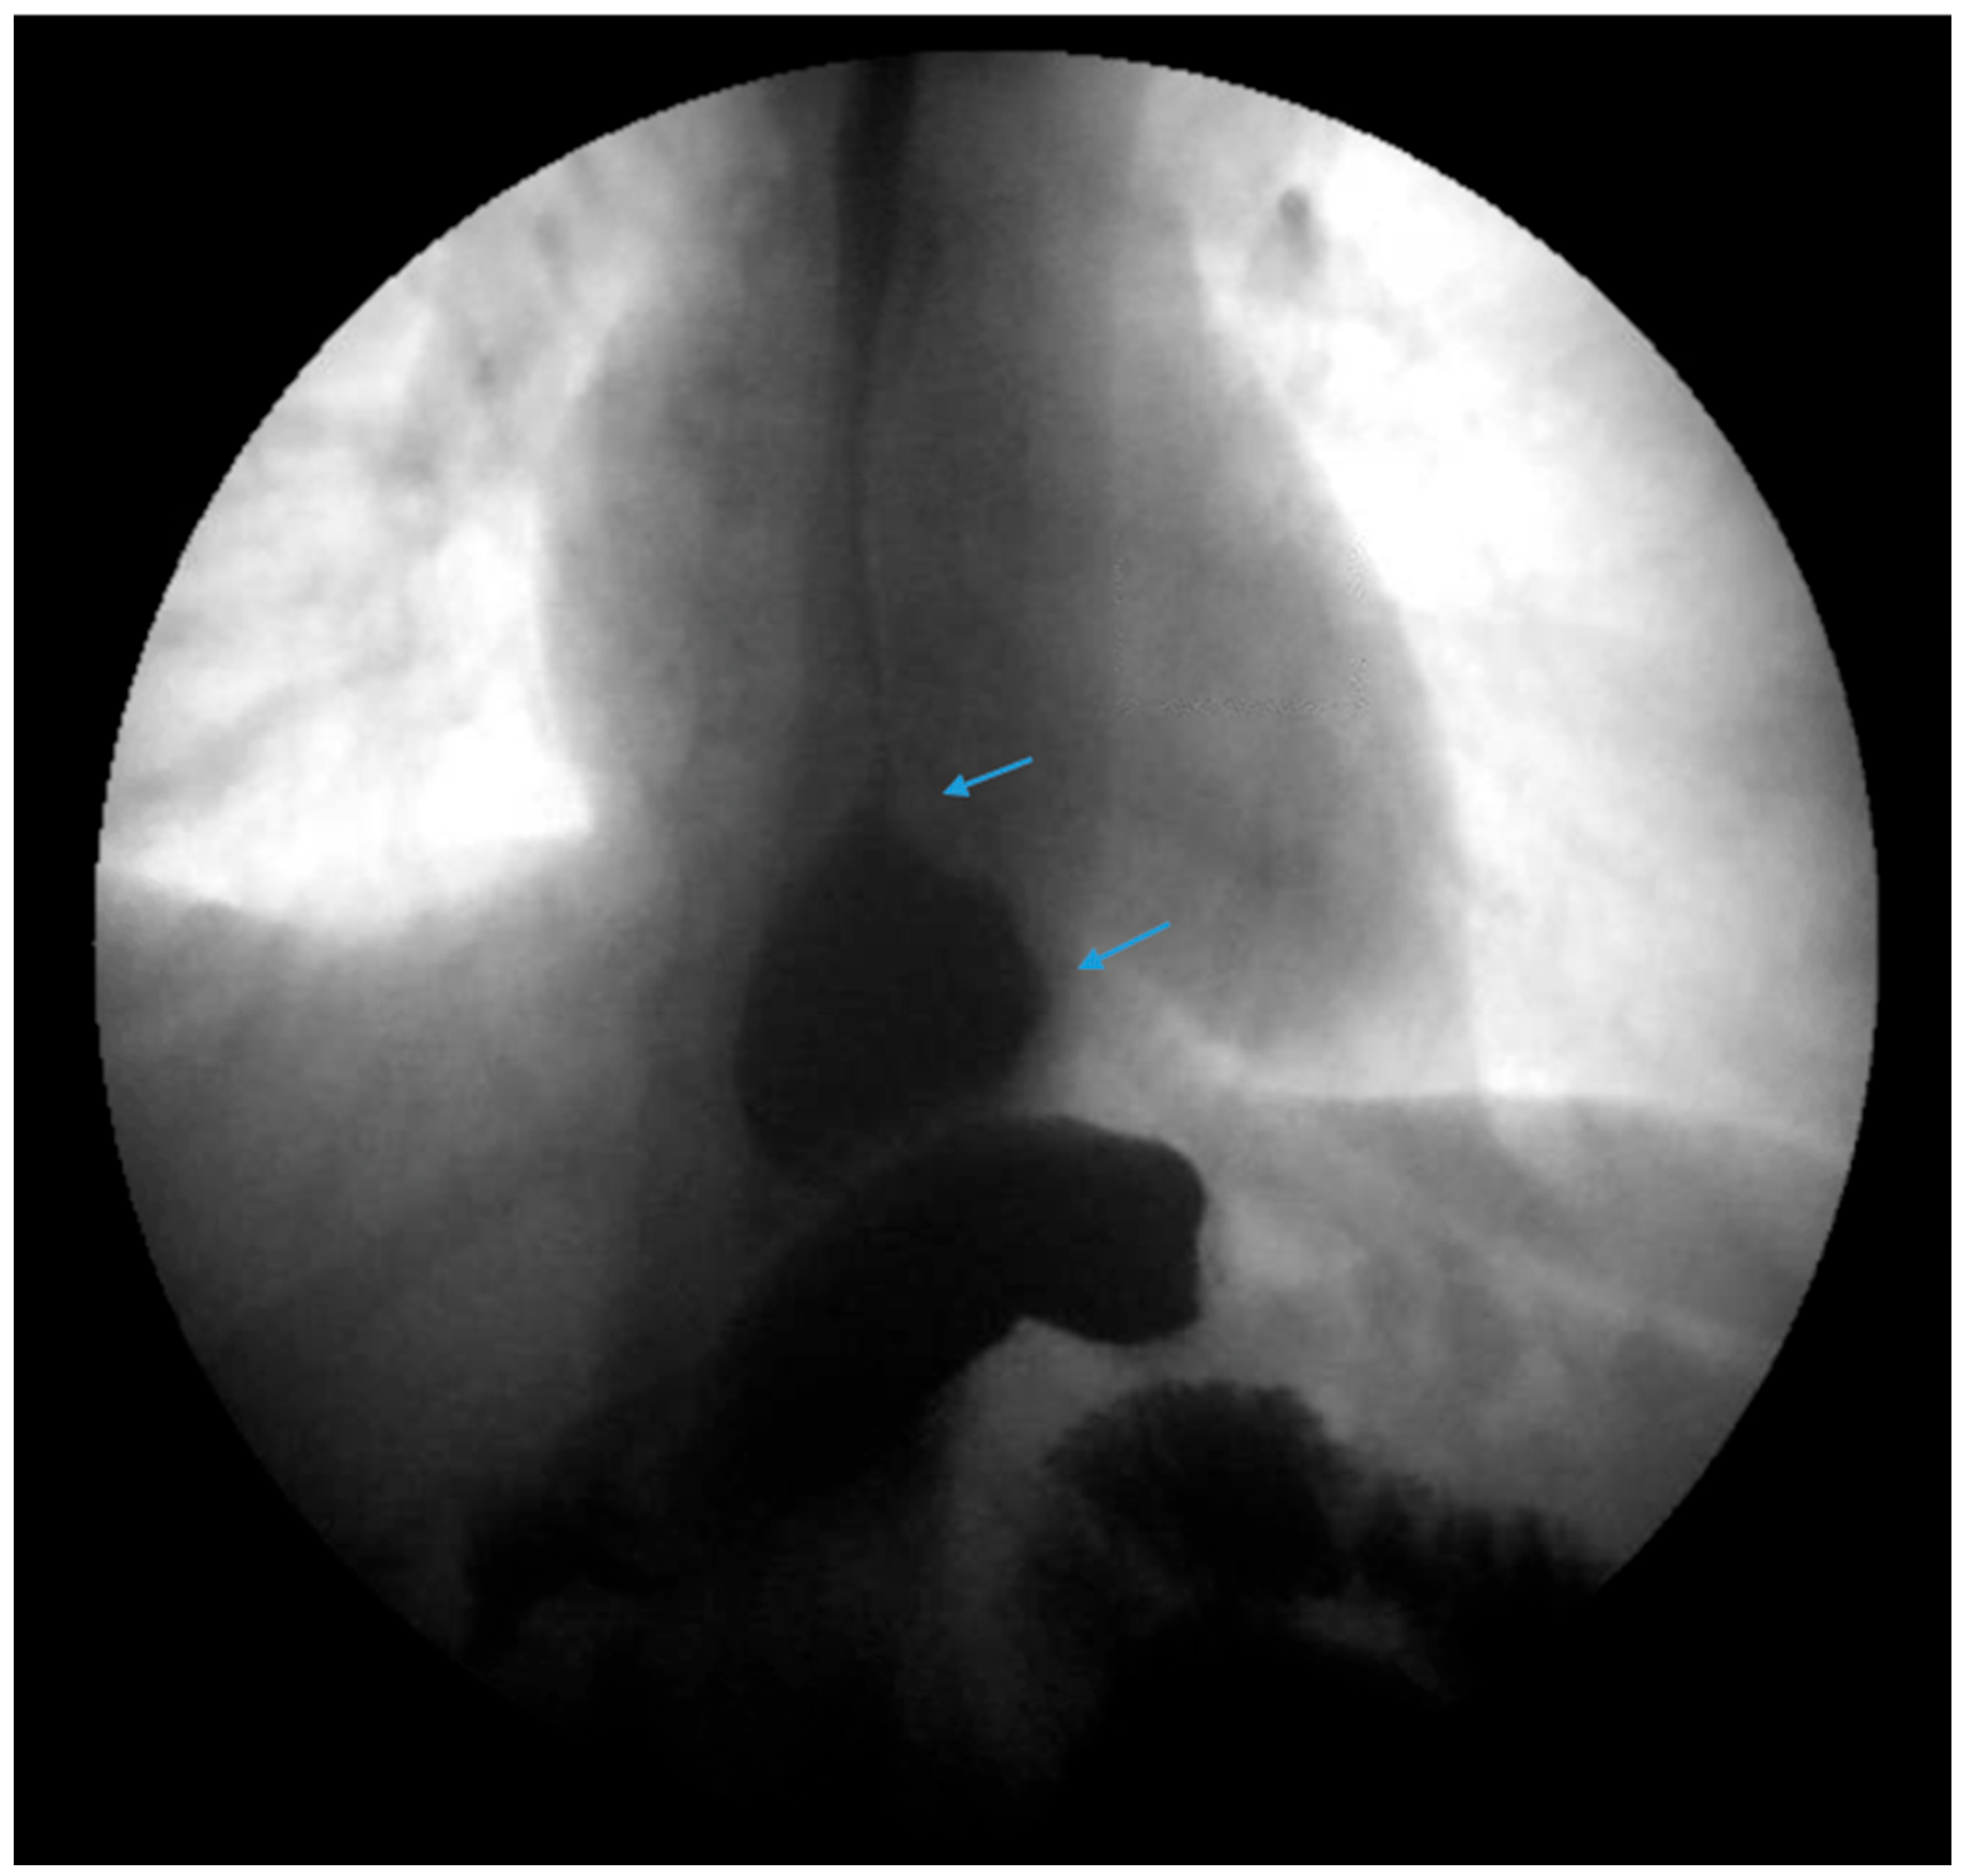

Figure 7.

An upper gastrointestinal series reveals a small, sliding hiatal hernia (bottom arrow) in addition to gastroesophageal reflux disease (top arrow) in a patient following sleeve gastrectomy.

Figure 8.

An upper gastrointestinal series reveals a small, sliding hiatal hernia (bottom arrow) with spontaneous gastroesophageal reflux (top arrow) in a patient following sleeve gastrectomy.

Due to the prevalence of hiatal hernias in the bariatric population, several studies have explored GERD outcomes when SG is combined with either fundoplication or hiatal hernia repair (Figure 7 and Figure 8) [82,83,84,85,86,87,88,89,90,91,92,93,94]. The authors acknowledge that the published studies on SG combined with either fundoplication or hiatal hernia repair are investigational, with a limited sample size and variable follow-up. We summarize the published data regarding SG combined with either fundoplication or hiatal hernia repair to highlight experimental approaches to GERD post-SG beyond conversion to RYGB with hiatal hernia repair.